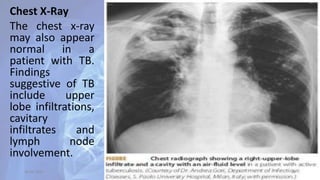

Chest X-Ray

The chest x-ray

may also appear

normal in a

patient with TB.

Findings

suggestive of TB

include upper

lobe infiltrations,

cavitary

infiltrates and

lymph node

involvement.

Chest X-Ray The chestx-ray may also appear normal in a patient with TB. Findings suggestive of TB include upper lobe infiltrations, cavitary infiltrates and lymph node involvement. 30-04-2020 32